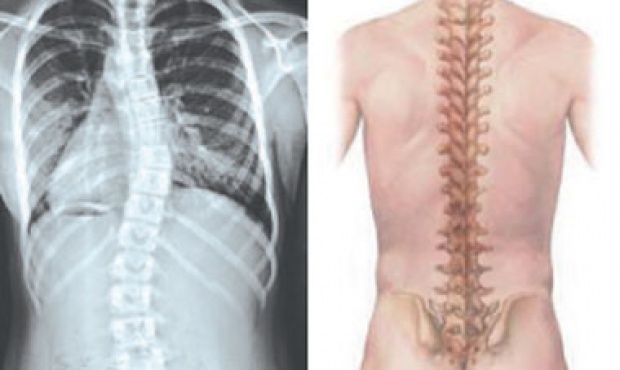

El doctor Juan Pablo Boiero, explicó que la “Escoliosis Idiopática” en niños y adolescentes es una curva con desplazamiento lateral de la columna vertebral, que le da a esta un aspecto de “S” o de “C” en vez de una “I” recta.

Señaló que el término “Idiopático” significa que la causa de este trastorno es desconocida (en la mayoría de los casos). Hay curvas de escoliosis que miden por lo menos 10° en el 1.5% al 3.0% de la población, otras curvas que superan 20° en el 0.3% al 0.5% de la población y menos frecuentes son las que superan 30° en el 0.2% al 0.3% de la población. El caso de esta paciente fue severo ya que la curva escoliótica era de 54º.

La escoliosis se confirma con una radiografía de la columna, posteriormente el médico mide el grado de la curva que aparece en la placa. Si no se tratan, las curvas de escoliosis que superan los 50º pueden llevar a problemas a largo plazo, es posible que ocurra un deterioro progresivo de la curva escoliótica, que en algunos pacientes consigue llevar a reducción de la capacidad pulmonar y desarrollo de enfermedad pulmonar restrictiva, dijo el profesional.

Boiero, indicó que “la cirugía consistió en el implante de una prótesis de titanio en la columna de la niña, compuesto de unas varillas, ganchos, tornillos y/o alambres para enderezar la columna de la paciente, la cual se realizó con total éxito”.